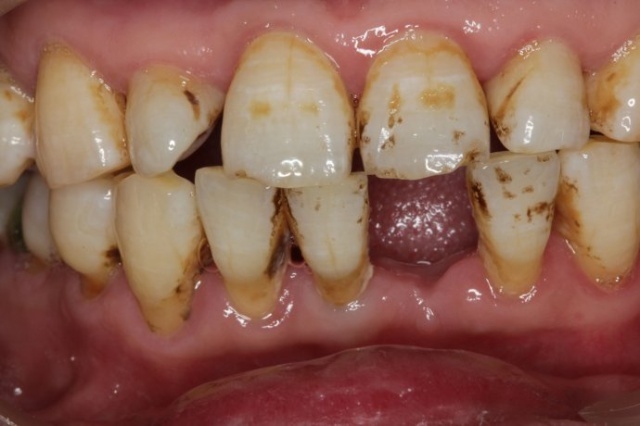

術(shù)前:

經(jīng)過朋友的介紹,也做了一些了解之后,我決定帶爸爸來正夫口腔做種植牙,來醫(yī)院后,爸爸做了一系列檢查,確定身體沒問題,就進(jìn)行了第一階段的手術(shù),術(shù)前爸爸有一些緊張,但在和醫(yī)生進(jìn)行了全面的溝通之后,爸爸的緊張情緒也徹底消除了,于是就開始準(zhǔn)備手術(shù),手術(shù)時(shí)間差不多有三個(gè)小時(shí)。